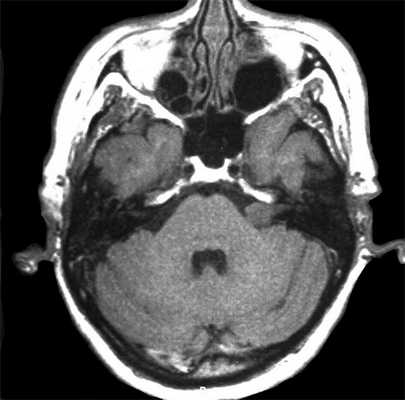

На Т2-взвешенных МРТ головного мозга невриномы имеют округлую или овальную форму, изоинтенсивны или слегка гиперинтенсивнее белого вещества, хорошо видны на фоне яркого ликвора цистерны. Крупные опухоли могут подвергаться кистозной дегенерации и включать сосуды. Мелкие невриномы имеют компонент во внутреннем слуховом проходе и как бы “утолщают“ нерв на МРТ изображениях. Как показывает опыт МРТ СПб полностью внутриканальцевые невриномы встречаются редко. МРТ в СПб при шванномах мы проводим обычно с контрастированием. Контрастирование неврином при МРТ с контрастированием хорошее, обычно однородное. Нельзя забывать, что во внутреннем слуховом проходе также может быть воспалительный процесс (неврит), приводящий к сходной клинической симптоматике. При МРТ неврит виден как отёк нерва, имеется контрастное усиление на МР томограммах.

МРТ головного мозга. Невринома слухового нерва слева с внутриканальцевым компонентом. Аксиальные Т1-зависимая МРТ, Т1-зависимая МРТ с контрастированием, и корональная Т1-зависимая МРТ с контрастированием.